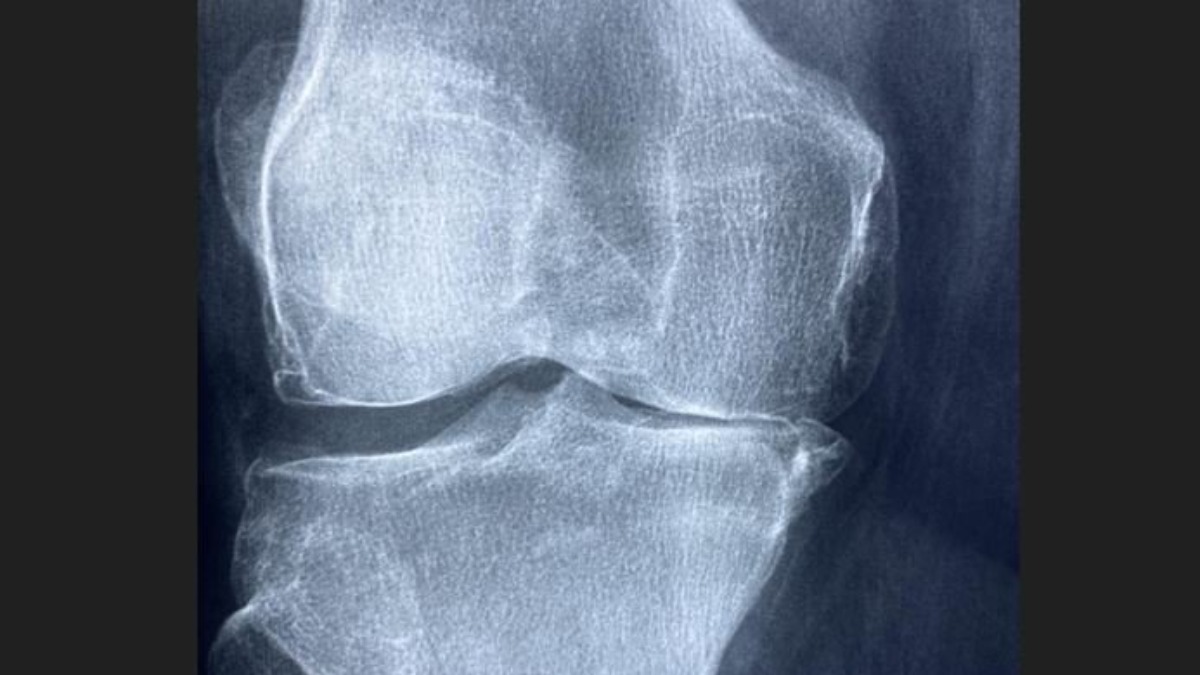

Njemački naučnici razvili gel koji može obnoviti zglobove bez operacije i implantata

U Njemačkoj su naučnici razvili revolucionarni gel koji može regenerisati zglobnu hrskavicu, nudeći nadu milionima osoba koje pate od artritisa i oštećenja zglobova.

Do sada su problemi sa zglobovima tretirani implantatima, metalnim zamjenama ili bolnim operacijama. Ovaj novi gel obećava budućnost u kojoj tijelo samo može prirodno obnoviti oštećeno tkivo, bez implantata, invazivnih procedura i dugog oporavka.

Hrskavica je glatko, amortizujuće tkivo koje omogućava zglobovima nesmetano kretanje. Kada se ošteti, rijetko se prirodno obnavlja, ostavljajući pacijente sa ukočenošću, oticanjem i dugotrajnim bolom.

Do sada su rješenja bila privremena – lijekovi – ili trajna – zamjena zgloba. Njemački gel značajno mijenja ovu situaciju.

Kada se injektuje u zglob, gel djeluje kao struktura koja podstiče vlastite ćelije tijela na regeneraciju zdrave hrskavice. S vremenom, zglob ponovo dobija prirodnu amortizaciju i pokretljivost, funkcionišući kao da nikada nije bio oštećen. Za razliku od umjetnih implantata koji se mogu trošiti ili zahtijevati zamjenu, ovaj pristup fokusira se na pravu regeneraciju tkiva.

Rani rezultati su obećavajući: pacijenti pokazuju poboljšano kretanje, smanjen bol i dugoročno iscjeljenje koje do sada nije bilo moguće. Ako veći klinički testovi potvrde ove nalaze, gel bi mogao postati novi standard u liječenju oštećenja zglobova, zamjenjujući operacije.

Primjena ovog otkrića daleko nadilazi artritis – sportisti sa povredama, starije osobe sa smanjenom pokretljivošću i svi koji imaju oštećenja zglobova uskoro bi mogli imati pristup tretmanu koji obnavlja, a ne zamjenjuje izgubljeno tkivo.